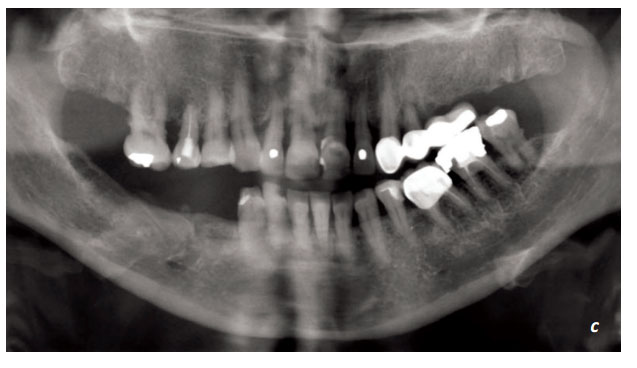

Resim 1.2. a, b, c. Önceden yapılmış restorasyonlar ve durumları belirlenmelidir. Bunların, uygunlukları ve değiştirilip değiştirilmeyeceği konusunda karar verilmelidir. Alınan radyografiler, klinik değerlendirmeyi desteklerler.

Resim1. 4. a, b. 15 yıl önce uygulanmış implantlar ve protetik restorasyonların, kontrol amacı ile panoramik radyografi ile muayenesinde, tüm tedavi ve restorasyonların sorunsuz olduğu görülmüştür.